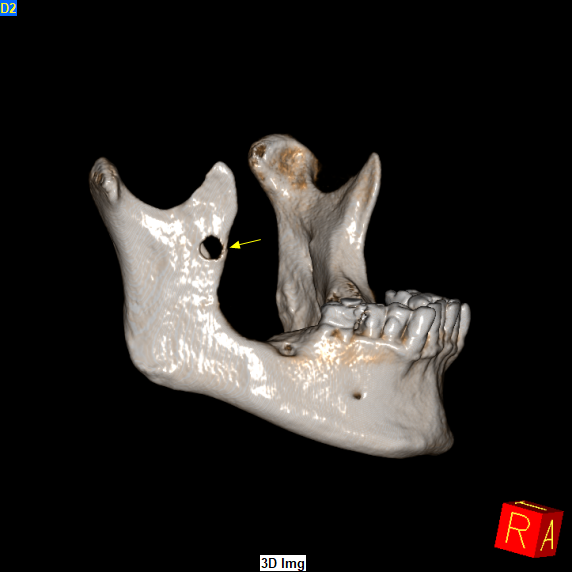

Τον Φεβρουάριο του 2024 ο ασθενής παραπέμφθηκε για CBCT άνω και κάτω γνάθου προκειμένου να προχωρήσει σε οδοντιατρικές εργασίες. Στο CBCT παρατηρήθηκε η παρουσία μικρού μεγέθους υπόπυκνης αλλοίωσης στο πρόσθιο χείλος του δεξιού κλάδου της κάτω γνάθου η οποία είχε προκαλέσει λύση των συμπαγών πετάλων.

Όπως αποδείχθηκε επρόκειτο για Αδαμαντινοβλάστωμα, και συνεπώς υποτροπή της αρχικής βλάβης που πρωτοεμφανίστηκε προ 3ετίας!